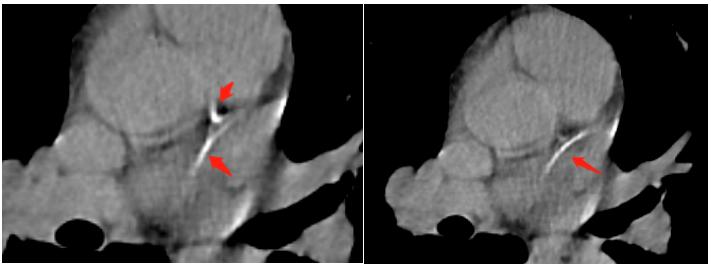

男性,58岁,身高166cm,体重72.3kg,BMI 26.2kg/m2,血压130/80mmHg,腰围86cm。平时蔬菜水果摄入可,不吸烟饮酒,间歇运动。1年余前常规体检冠脉CTA提示其中一支血管狭窄约70%,目前口服阿托伐他汀20mg/天+依折麦布10mg/天,阿司匹林100mg/天,最近1月停服阿司匹林。

本例冠脉多支钙化,以前降支明显,即使未行冠脉CTA,也提示存在高危缺血性心血管事件风险,应强化降胆固醇及抗血小板治疗(冠脉钙化评分≥100可以口服阿司匹林81/100mg/天)。

建议阿托伐他汀加量至40mg/天+依折麦布10mg/天,目标LDL-C<1.8mmol/L,ApoB<0.8g/L,无明显出血风险应维持阿司匹林100mg/天抗血小板,3年后复查冠脉钙化积分,结合症状必要时复查冠脉CTA或DSA冠脉造影。